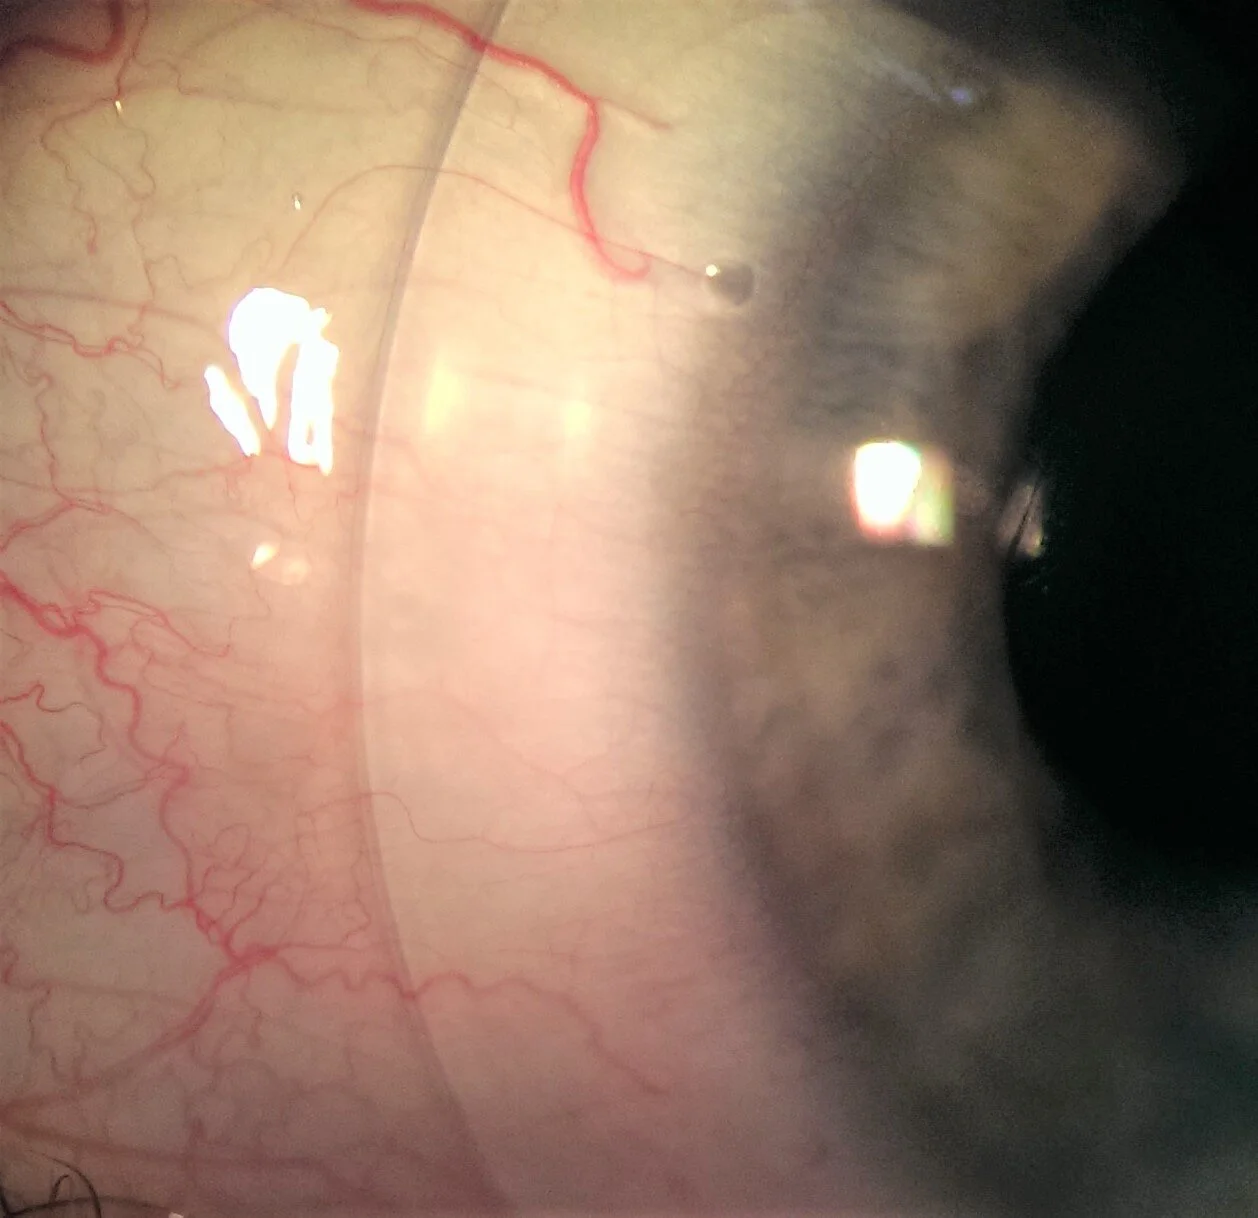

Scleral lenses are large rigid gas permeable (RGP) contact lenses that cover the entire cornea, landing on the conjunctiva and sclera. This design provides a secure and stable fit, offering unique advantages for various eye conditions.

• Irregular Corneas: Providing a stable and comfortable option for conditions like keratoconus and pellucid marginal degeneration.